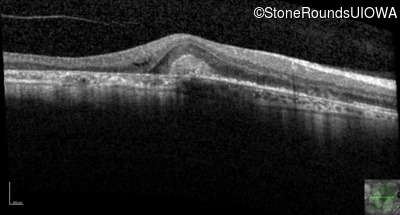

AR Stargardt Disease (IIA)

Age at visit: 51 years

This 51 year old woman first experienced some abnormality in her distance vision when she was 27 years old. She feels that her vision has been stable since that time.

Diagnosis & molecular findings

Disease Gene Allele 1 variant(s) Allele 2 variant(s) Inheritance mode

AR Stargardt Disease ABCA4 Gly1507Arg GGG>AGG IVS42+1 G>A AR